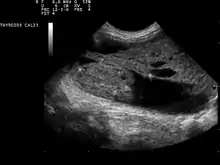

Thyroid nodule

Ultrasound artifacts showing a "comet tail" from a colloid nodule indicate a benign nodule

Ultrasound imaging is useful as the first-line, non-invasive investigation in determining the size, texture, position, and vascularity of a nodule, accessing lymph nodes metastasis in the neck, and for guiding fine needle aspiration cytology (FNAC) or biopsy. Ultrasonographic findings will also guide the indication to biopsy and the long term follow-up.[10] High frequency transducer (7–12 MHz) is used to scan the thyroid nodule, while taking cross-sectional and longitudinal sections during scan. Suspicious findings in a nodule are hypoechoic, ill-defined margins, absence of peripheral halo or irregular margin, fine, punctate microcalcifications, presence of solid nodule, high levels of irregular blood flow within the nodule[11] or "taller-than-wide sign" (anterior-posterior diameter is greater than transverse diameter of a nodule). Features of benign lesion are: hyperechoic, having coarse, dysmorphic or curvilinear calcifications, comet tail artifact (reflection of a highly calcified object), absence of blood flow in the nodule, and presence of cystic (fluid-filled) nodule. However, the presence of solitary or multiple nodules is not a good predictor of malignancy. Malignancy is only diagnosed when ultrasound findings and FNAC report are suggestive of malignancy.[11] The TI-RADS (Thyroid Imaging Reporting and Data Systems) are sonographic classification systems which describe the suspicious findings of thyroid nodules.[12] It was first proposed by Horvath et al.,[13] based on the BI-RADS (Breast Imaging Reporting and Data System) concept. Several systems were subsequently proposed and adopted by international scientific societies. Their main aims are to characterize the risk of malignancy of nodules to better select nodules to submit to fine-needle aspiration cytology.[14] Another imaging modality, which is ultrasound elastography, is also useful in diagnosing thyroid malignancy especially for follicular thyroid cancer. However, it is limited by the presence of adequate amount of normal tissue around the lesion, calcified shell around a nodule, cystic nodules, coalescent nodules.[15]